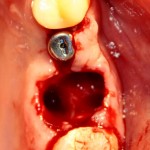

Удаляется 16 зуб. Параллельно, фиксируется формирователь десны на установленный двумя месяцами ранее имплантат 15 зуба:

Точка ориентира для позиционирования импланта – межкорневая перегородка. Несмотря на то, что установка импланта в одну из альвеол позволило бы избежать синуслифтинга, делать это крайне не желательно, так как подобное позиционирование создаст ряд серьезных проблем при протезировании и дальнейшей эксплуатации протетической конструкции

Дополнительным латеральным доступом проводится операция синуслифтинга. Субантральное пространство заполняется ксенотрансплантатом Bioss в смеси с аутокостной стружкой в пропорции 2:1. Также данным материалом заполняются лунки корней зубов, хотя какой-то большой необходимости в этом нет. Устанавливается имплантат Friadent Xive Диаметром 5.5 и длиной 11 мм.

Убирается имплантодержатель:

В данном случае первичная стабильность импланта крайне не высокая. Поэтому принято решение отказаться от установки формирователя десны.

Лунка зуба закрывается коллагеновой мембраной BioGide, которая фиксируется к импланту заглушкой через предварительно сделанное отверстие.